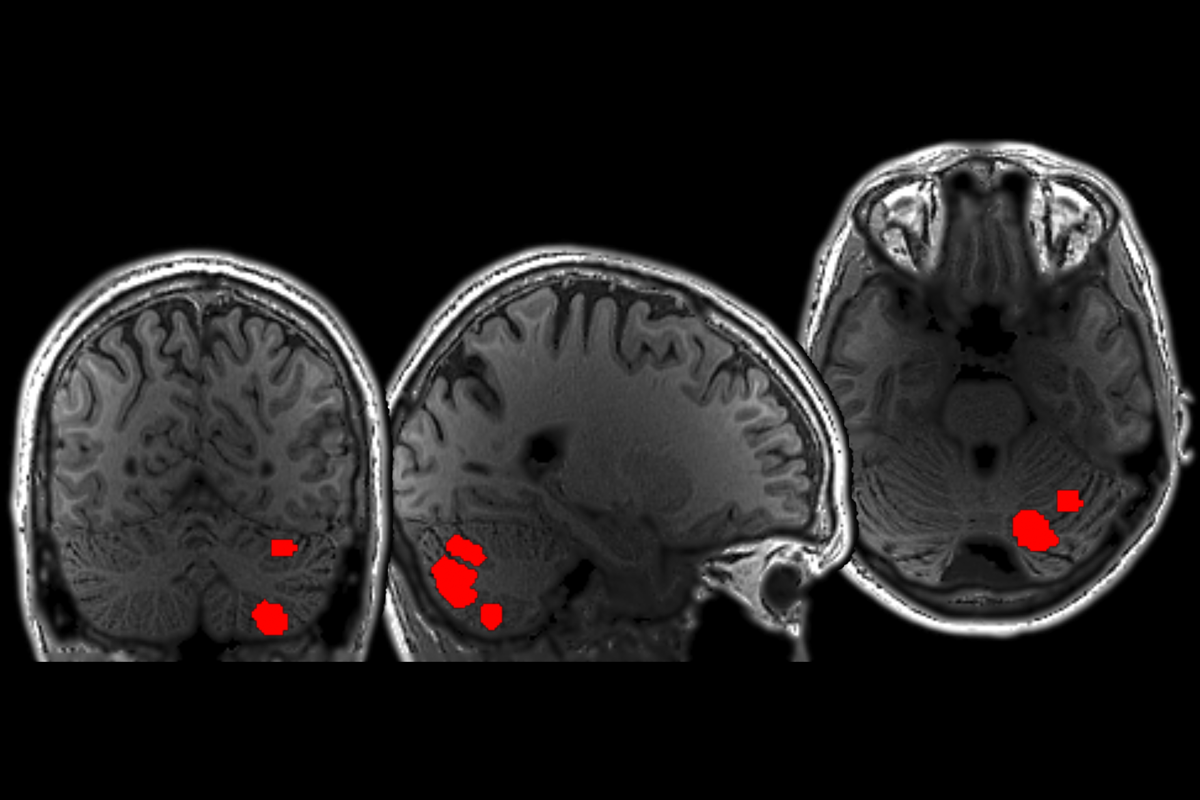

A region of the cerebellum shows language specificity akin to that of cortical language regions, indicating that it might be part of the broader language network, according to a new brain-imaging study.

Four cerebellar regions activated robustly when participants performed language-related tasks, such as reading passages of text or listening to someone else reading the passages aloud, in line with previous work. But only one region responded exclusively to these language-related tasks; it did not activate during a variety of nonlinguistic tasks—including movement, arithmetic tasks and a spatial working memory task—or when participants listened to music or watched videos of faces and bodies.

The language-selective region in the cerebellum engages during both language comprehension and production—something previously thought to be unique to neocortical areas. And it strongly connects to the neocortical language network, the work suggests. The findings were published last month in Neuron.

The cerebellar region is more selectively tuned to meaningful sentences than the neocortical language areas are. Grammatically accurate, meaningful sentences elicited strong responses in the neocortical language areas and the language-exclusive cerebellar area, but the cerebellar area was less responsive than the cortex to grammatical but meaningless “jabberwocky” sentences. The cerebellum may perform a different computation than the neocortical language areas, the results suggest.